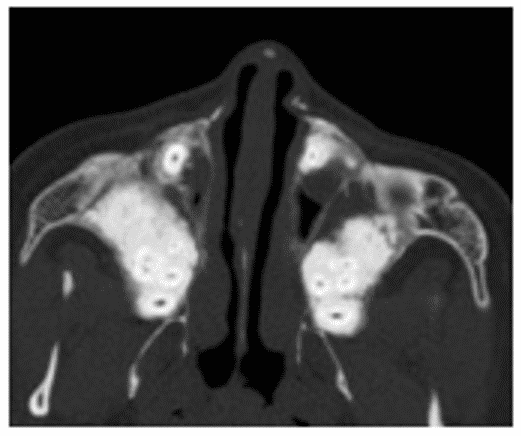

При фиброзной дисплазии верхней челюсти патологический процесс сравнительно быстро распространяется на верхнечелюстной синус, альвеолярный, скуловой и лобный отростки. При вовлечении в процесс медиальной стенки верхнечелюстной пазухи может наблюдаться сужение или облитерация носослезного канала, носовых ходов, деформация перегородки носа (рисунок 8).

Рис. 8. КТ околоносовых пазух, аксиальная проекция (А) и реконструкция в коронарной плоскости (Б). Фиброзная дисплазия обеих верхнечелюстных пазух с поражением скуловых отростков (остеоцементодисплазия)

Пораженная верхнечелюстная кость и скуловые отростки имеют неоднородную структуру, на фоне которой вокруг корней зубов определяются обширные высокоплотные зоны (цементикли).